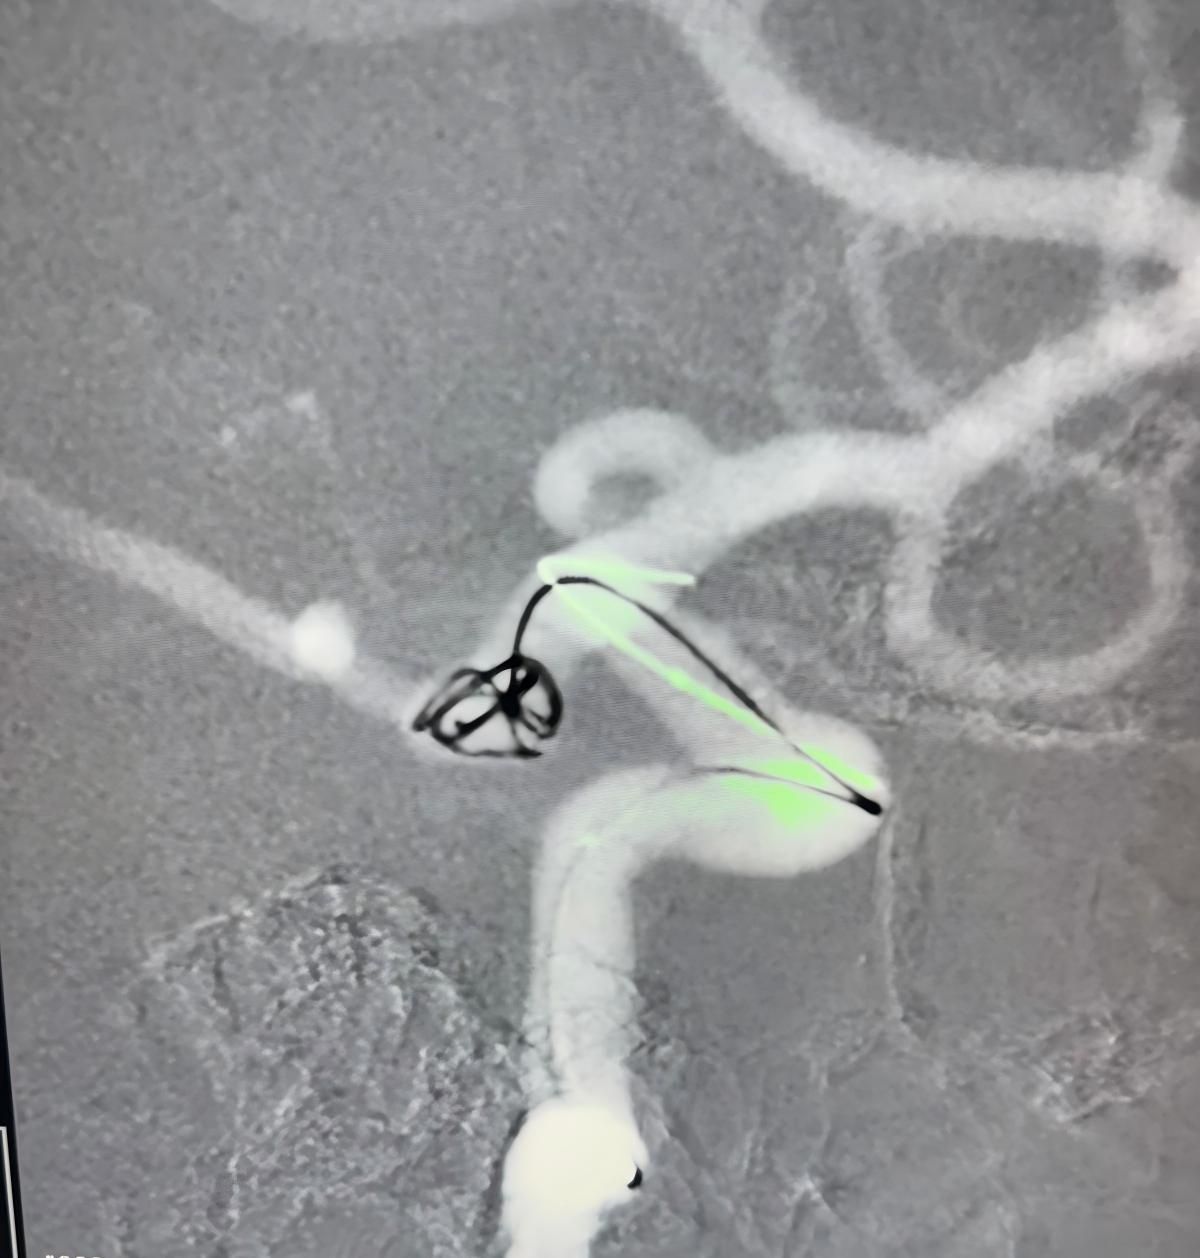

The treatment utilized the Nuva® Flow Diverter (TJED-D 5.0–14), Perdenser® 3D coil, and Frepass® Microcatheter (TJMC18 Plus) for a posterior communicating artery aneurysm.

Dr. Mutis highlighted the excellent visibility of the device and noted that retrieving was smooth. He expressed great satisfaction with the final outcome.